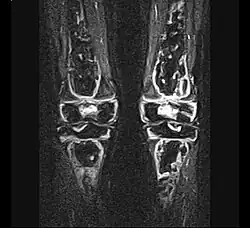

- Stadium ARCO 0

Im Anfangsstadium sind in konventionellen Röntgenaufnahme keine krankhaften Veränderungen zu erkennen. In seltenen Fällen ist eine dezente Auflockerung der Knochenfeinstruktur (Trabekel) in dem betroffenen Areal zu erkennen: das Ausmaß dieser Auflockerung ist jedoch zumeist so gering, dass es nicht sicher erkannt werden kann. In der Kernspintomographie (MRT) ist in diesem Stadium ein Bild analog dem Knochenmarködem (KMÖ, transiente Osteoporose; bone marrow edema, BME) zu erkennen. Unter Verwendung der short tau inversion recovery (STIR) Aufnahmesequenz wird eine Signalhyperintensität (helles Aufleuchten im Graustufen-Kernspinbild) festgestellt (vergleiche Bild 1a und 2 helle Ränder). Eine sichere Unterscheidung zwischen dem prinzipiell reversiblen Bild eines KMÖ/BME und dem Stadium ARCO I einer aseptischen Knochennekrose ist nicht mittels des Kernspintomogramms möglich.

_-_MR_Coronal_STIR_-_child_13_yrs_after_ALL_-_01.jpg)